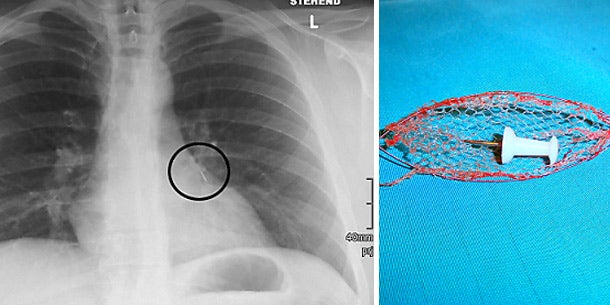

Der Mühlviertler hatte die zwei Zentimeter lange Nadel zwischen den Lippen eingeklemmt, um die Hände freizuhaben. Dann fiel ihm die Wasserwaage zu Boden, er erschrak und holte tief Luft. Dabei atmete er die Nadel mit ein. Sie steckte mit dem Griff nach unten in der Lunge fest und verschloss einen Bronchienstamm, wie ein Röntgen im Krankenhaus Freistadt zeigte. Der Patient wurde zu den Elisabethinen nach Linz überstellt.